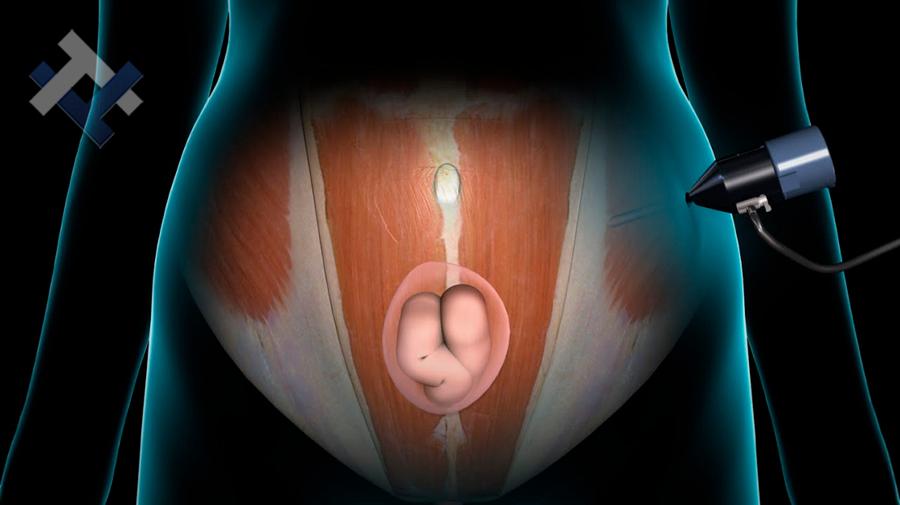

Ο Γενικός Χειρουργός Λιάγκος Γεώργιος MD PhD εκτελεί τις επεμβάσεις Λαπαροσκοπικά, Ενδοσκοπικά, Ανοιχτά Ελάχιστα Επεμβατικά και με Laser. Η θεραπεία εξατομικεύεται σε κάθε ασθενή ανάλογα με τις ανάγκες του. Αναλαμβάνει περιπτώσεις όπως κήλες και κοιλιοκήλες (αντιμετώπιση βουβωνοκήλης, αντιμετώπιση ομφαλοκήλης, θεραπεία επιγαστρικής κήλης, κήλη των αθλητών (Σύνδρομο κοιλιακών προσαγωγών), αντιμετώπιση μετεγχειρητικής κήλης, θεραπεία Μηροκήλης), πέτρες στη χοληδόχο κύστη, λαπαροσκοπική χολοκυστεκτομή, αντιμετώπιση Κύστη Κόκκυγος με λέιζερ (laser), παθήσεις πρωκτού, χειρουργική laser σύγχρονων κυκλικών ινών (αιμορροΐδες αντιμετώπιση, θεραπεία αιμορροϊδων με laser (LHP), αφαίρεση αιμορροΐδων με υπερήχους (HALL-RAR), χωρίς Χειρουργείο με ελαστικούς δακτυλίους (Τεχνική BARON-RBL), θεραπεία ραγάδας πρωκτού (Ραγάδα δακτυλίου), θεραπεία περιεδρικού συριγγίου, θεραπεία περιεδρικού αποστήματος, κονδυλώματα πρωκτού Θεραπεία, δερματικό ράκος (Skin tag) εκτομή, αντιμετώπιση Kνησμού, καρκίνος πρωκτού θεραπεία), παθήσεις Δέρματος, χειρουργική με laser CO2, αφαίρεση μορφωμάτων δέρματος - βιοψίες, αφαίρεση ελιάς (Σπίλου), σμηγματογόνος κύστης θεραπεία, αφαίρεση λιπώματος, είσφρυση όνυχος χειρουργείο, καρκίνος δέρματος θεραπεία, οξεία σκωληκοειδίτιδα, παθήσεις Λεπτού και Παχέος Εντέρου, ειλεός λεπτού εντέρου, εκκολπωμάτωση (Εκκολπωματίτιδα) σιγμοειδούς, καρκίνος παχέος εντέου, κολοστομίες, port χημειοθεραπείας κ.α.

Ο Γενικός Χειρουργός Λιάγκος Γεώργιος MD PhD εκτελεί τις επεμβάσεις Λαπαροσκοπικά, Ενδοσκοπικά, Ανοιχτά Ελάχιστα Επεμβατικά και με Laser. Η θεραπεία εξατομικεύεται σε κάθε ασθενή ανάλογα με τις ανάγκες του. Αναλαμβάνει περιπτώσεις όπως κήλες και κοιλιοκήλες (αντιμετώπιση βουβωνοκήλης, αντιμετώπιση ομφαλοκήλης, θεραπεία επιγαστρικής κήλης, κήλη των αθλητών (Σύνδρομο κοιλιακών προσαγωγών), αντιμετώπιση μετεγχειρητικής κήλης, θεραπεία Μηροκήλης), πέτρες στη χοληδόχο κύστη, λαπαροσκοπική χολοκυστεκτομή, αντιμετώπιση Κύστη Κόκκυγος με λέιζερ (laser), παθήσεις πρωκτού, χειρουργική laser σύγχρονων κυκλικών ινών (αιμορροΐδες αντιμετώπιση, θεραπεία αιμορροϊδων με laser (LHP), αφαίρεση αιμορροΐδων με υπερήχους (HALL-RAR), χωρίς Χειρουργείο με ελαστικούς δακτυλίους (Τεχνική BARON-RBL), θεραπεία ραγάδας πρωκτού (Ραγάδα δακτυλίου), θεραπεία περιεδρικού συριγγίου, θεραπεία περιεδρικού αποστήματος, κονδυλώματα πρωκτού Θεραπεία, δερματικό ράκος (Skin tag) εκτομή, αντιμετώπιση Kνησμού, καρκίνος πρωκτού θεραπεία), παθήσεις Δέρματος, χειρουργική με laser CO2, αφαίρεση μορφωμάτων δέρματος - βιοψίες, αφαίρεση ελιάς (Σπίλου), σμηγματογόνος κύστης θεραπεία, αφαίρεση λιπώματος, είσφρυση όνυχος χειρουργείο, καρκίνος δέρματος θεραπεία, οξεία σκωληκοειδίτιδα, παθήσεις Λεπτού και Παχέος Εντέρου, ειλεός λεπτού εντέρου, εκκολπωμάτωση (Εκκολπωματίτιδα) σιγμοειδούς, καρκίνος παχέος εντέου, κολοστομίες, port χημειοθεραπείας κ.α.